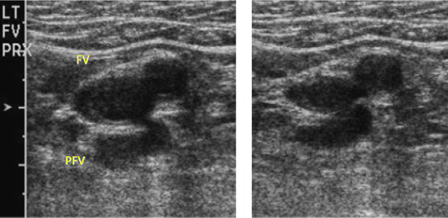

- venous duplex ultrasound (DUS)

- Doppler venous flow testing